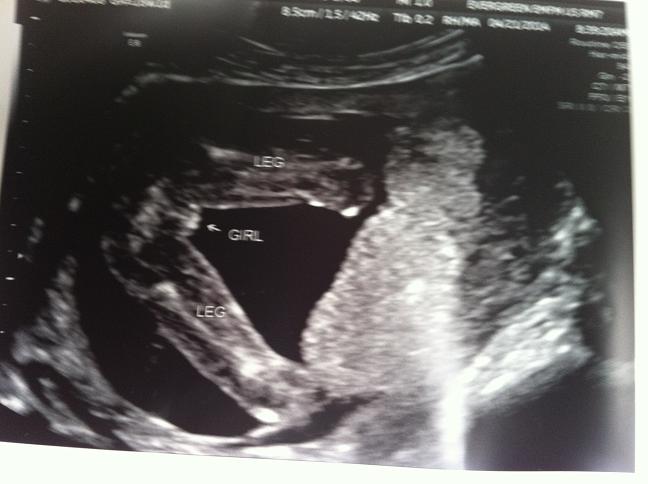

[ATTACH=CONFIG]18319Attachment 18321 Everyone said girl at 13 weeks and they were right!!